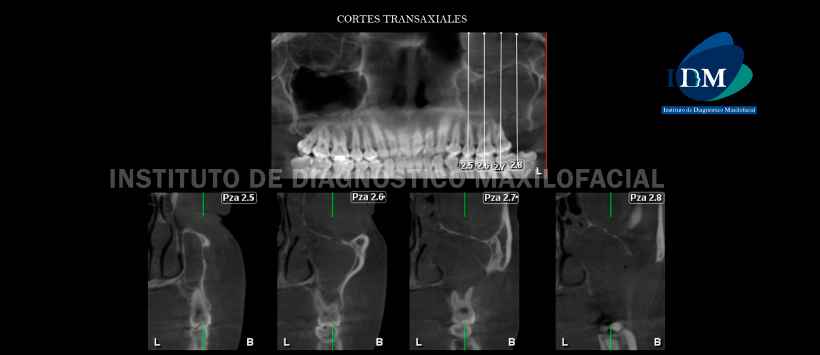

A la evaluación de la tomografía volumétrica (CBCT) en cortes coronales (Figura 2), sagitales (Figura 3), axiales (Figura 4) y transaxiales (Figura 5) se evidencia pérdida del reborde óseo alveolar de zona de pieza 28 asociado a una solución de continuidad hacia el seno maxilar donde se aprecia la presencia de una lesión isodensa de límites parcialmente definidos, localizado en seno maxilar del lado izquierdo, con desplazamiento, adelgazamiento y erosión del piso y pared anterior del seno maxilar; así mismo la lesión se encuentra asociada a un contenido isodenso en resto del seno maxilar con compromiso de la pared medial, obliteración del ostium sinusal, compromiso de las celdillas etmoidales y seno frontal de la parte izquierda.